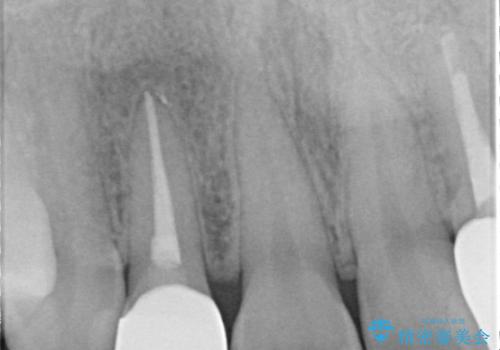

- 食べ物が歯間にはさまることを主訴に来院された患者様です。レントゲンより上顎両側切歯に根管治療が実施されていますが、被せ物が入っておらず、充填物に劣化像もみられました。歯の色の差も気にされていたのでオールセラミッククラウンにて治療いたしました。